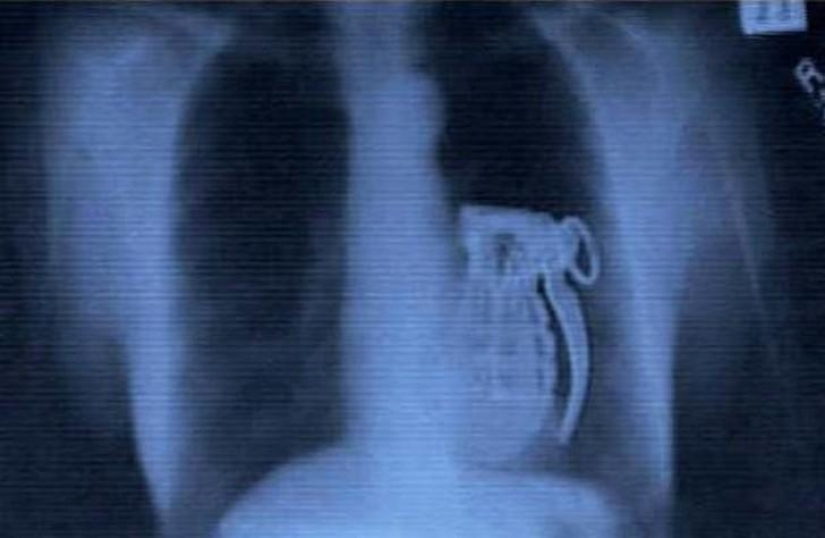

Granada.